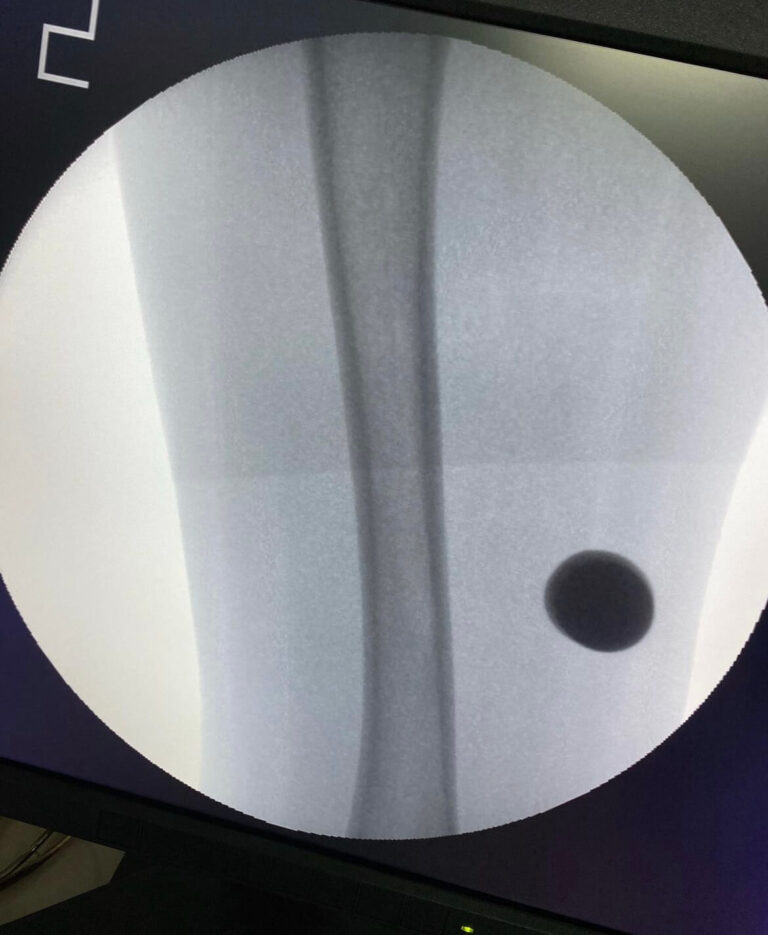

Современная сложная реконструктивная ортопедия в

мц «ЛАДИСТЕН КЛИНИК» город Киев Украина